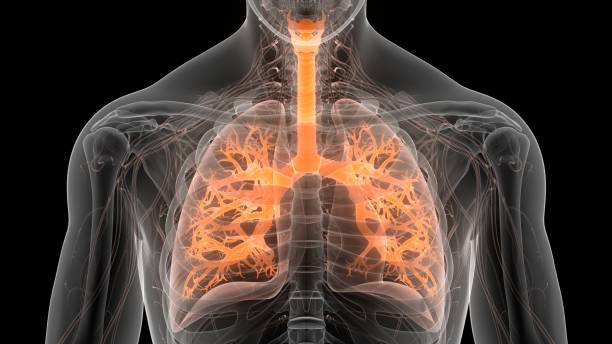

폐섬유화증은 폐조직 내 결손 및 염증에 의해 섬유화 과정이 일어나서, 건강한 폐조직이 염증과 섬유화에 대한 대체물질로 치환되는 질환입니다. 이로 인해, 섬유화된 조직은 신축성이 없고, 호흡기능이 저하됩니다. 따라서 다른 질병과 마찬가지로 초기에 적절한 치료를 받는 것이 중요하기 때문에 이번 시간에는 폐섬유화로 인한 증상들에 대해 정리해보겠습니다.